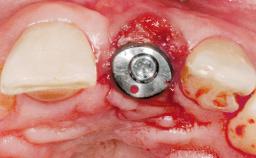

A 30-year-old female patient was referred to the office for the treatment of tooth 11. Her chief concern at the initial visit was to inquire, “Why is my tooth pink?” Upon clinical examination, it was determined that tooth 11 had a previous history of trauma and that the clinical crown had become noticeably pink in color as a result of internal resorption. This diagnosis was confirmed radiographically, indicating a large radiolucency involving the central and distal portions of the clinical crown. It was determined that restoration of this tooth was not possible, and that extraction was indicated. The presence of a mid-line diastema, which the patient wanted to reproduce, directed the treatment plan for tooth replacement utilizing a dental implant.

Type of Implants One-Piece|Reduced-Diameter

Placement Protocol Immediate implant placement

Tooth Site Maxillary incisor or canine

Socket Morphology Single-root socket

Socket Integrity Sufficient, with intact bone walls

Bone Volume Sufficient, with intact walls